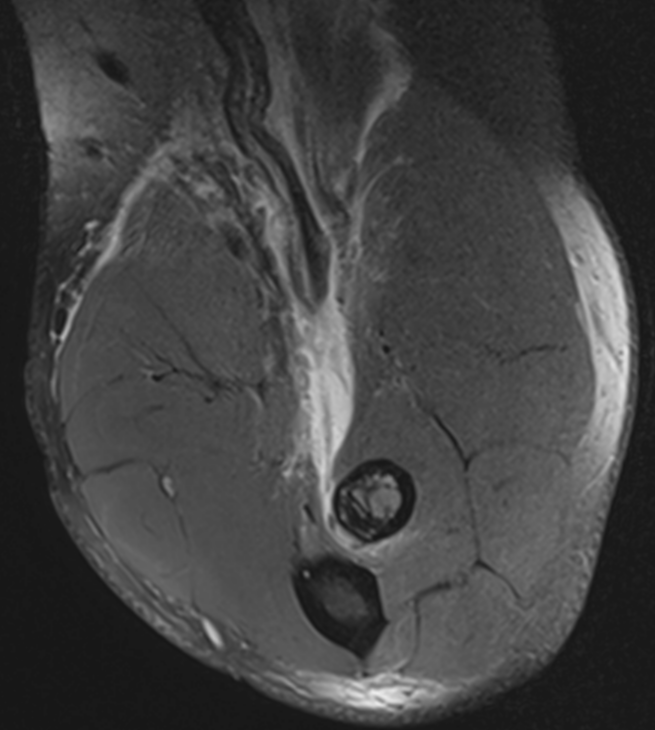

3. Torn distal biceps tendon (FABS View)